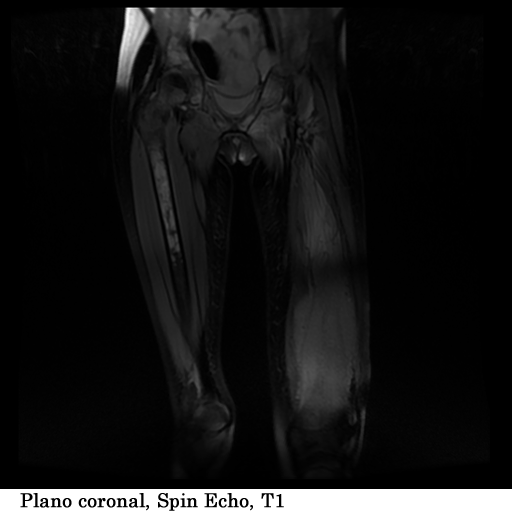

Paciente femenina, de 18 años de edad, con masa visible y palpable a nivel del tercio medio e inferior del fémur izquierdo, con un tiempo de evolución de 1 año, refiere dolor y limitación al movimiento.

TECNICA EMPLEADA

Se coloco al paciente en decúbito supino, utilizando una bobina fase array, haciendo adquisiciones en los planos axial, sagital y coronal, secuencias, spin echo, eco de gradiente e hibridas, potenciadas a T1, T2 y DP, secuencias Steer, y se obtuvieron imágenes con saturación de grasa.

HALLAZGOS IMAGENOLOGICOS

1. Edema de tejidos blandos que infiltra los músculos del muslo en su tercio medio y distal

2. Fractura patológica de tercio proximal de la diáfisis femoral izquierda

3. Engrosamiento del periostio del tercio medio y distal de la diáfisis femoral izquierda